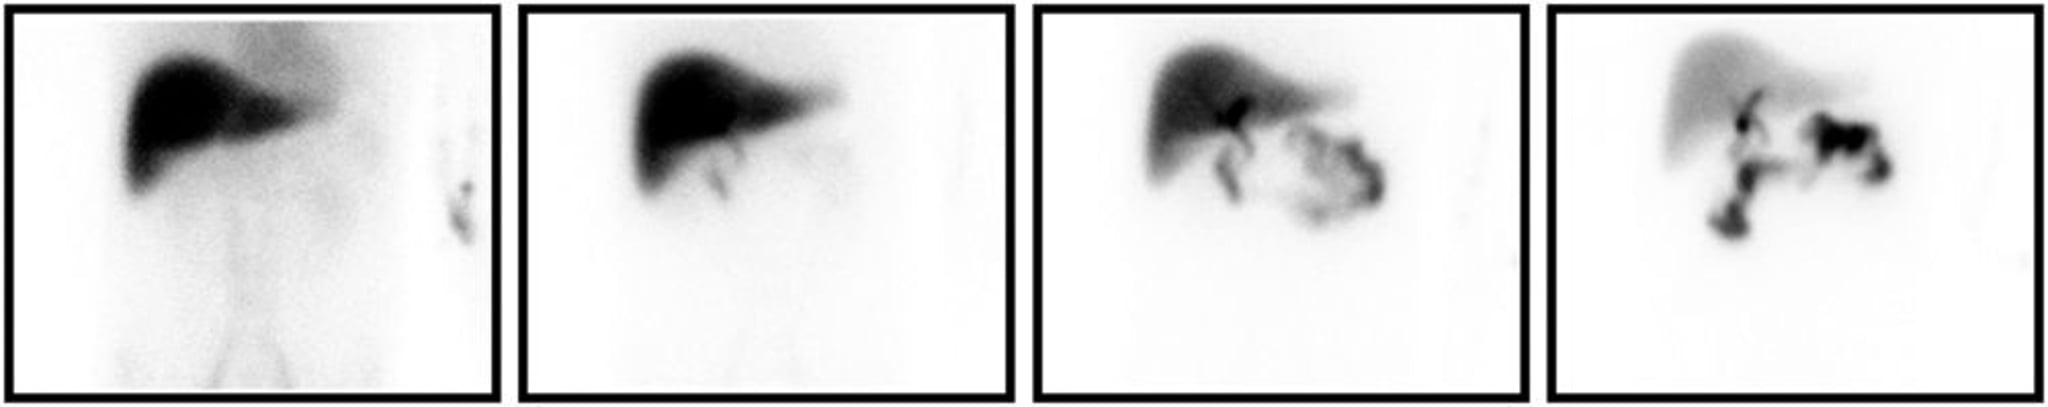

HIDA Scan

HIDA scan consistent with cholecystitis. Shown from left to right are the images acquired at 5, 15, 30, and 60 minutes following radiotracer injection. Even at late time points, there is nonfilling of the gallbladder.